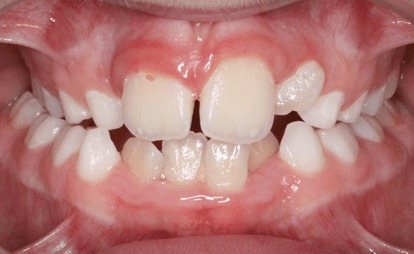

انواع کراس بایت (کراس بایت تک دندانی)

کراس بایت تک دندانی